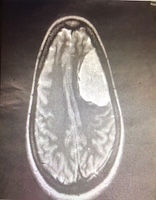

After the MRI, I was waiting back in the room for the results. A team of doctors entered the room and told me, “You have a very large meningioma and it needs to be removed tomorrow morning.” We are going to schedule your surgery. They showed me my scan and lo and behold… there was a very large mass in the left frontal lobe of my brain! I was in disbelief.

I ended up having a 7cmx4cm meningioma in my left frontal lobe, grade 2 at the age of 32.